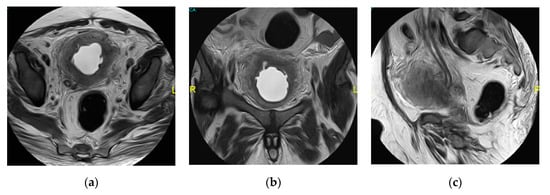

2.15. Acute Bacterial Prostatitis and Prostatic Abscess

| Prostatic abscess | Non enhancing fluid collection with peripheral or septal enhancement and non-enhancing central fluid. Possible extraprostatic extension |